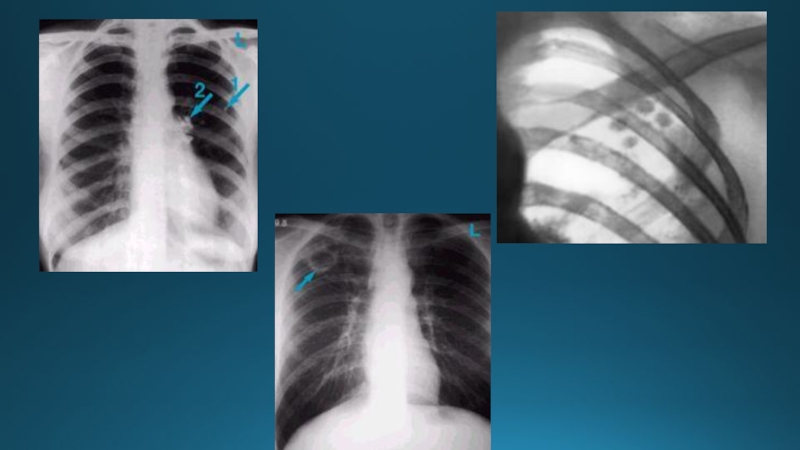

Слайд 50Пневмоторакс

Плевра қуысына газдың жиналуы, өкпе тінінің құлдырауына, көкірекортаның сау жаққа

ығысуымен, көкірекорта қан тамырларының қысылуымен, диафрагма куполының түсуімен жүретін патологиялық

процесс. Ол тыныс алу және қанайналым функциясының бұзылысына әкеледі.

Слайд 511. Кеуде қуысының немесе өкпенің механикалық жарақаты:

Кеуда қуысының жабық жарақаты

(қабырға сынықтарымен зақымдалуы)

Кеуде қуысының ашық жарақаты (сырттан енетін жарақат);

Жасанды пневмоторакс

–өкпе туберкулезі емі мақсатында қолданылатын пневматоракс (торакоскопиямен жүргізіледі).

2. Өкпе және кеуде қуысы ағзаларының аурулары:

Бейспецификалық сипатта – өкпенің буллезды ауруында (эмфизема) ауалы кисталардың жарылу салдарынан, өкпе абсцессінің плевра қуысына шығуы (пиопневмоторакс), өңештің кенеттен жарылуы.

Спецификалық сипатта – туберкулез кезінде казеозды ошақтардың, каверналар жарылуы себептерінен болатын пневмоторакс.